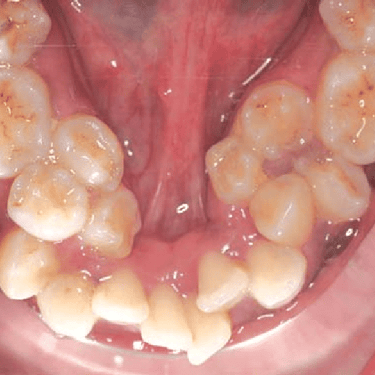

Dientes Supernumerarios

Los dientes supernumerarios son dientes adicionales que pueden aparecer en la boca y causar problemas de alineación o erupción de otros dientes.

Los pacientes pueden notar dientes adicionales en la boca, lo que puede causar apiñamiento o problemas estéticos.

El tratamiento incluye la extracción quirúrgica de los dientes supernumerarios.